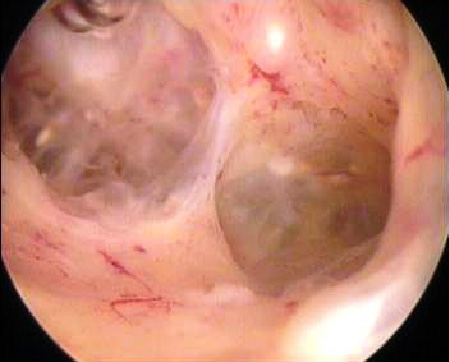

Hysteroskopische Myomresektion

Myome, die sich in der Gebärmutterhöhle befinden oder direkt unter der Gebärmutterschleimhaut (Endometrium) liegen, werden als intracavitäre bzw. submuköse Myome bezeichnet. Sie verursachen typischerweise Blutungsstörungen, z. B. in Form übermäßig starker und verlängerter Menstruationsblutungen. Diese können zu einer Blutarmut (Anämie) und zu einem Eisenmangel führen. Müdigkeit, Abgeschlagenheit und eine reduzierte Belastbarkeit sind häufig die Folgen.

Im Zusammenhang mit einer geplanten Schwangerschaft können intracavitäre und submuköse Myome unter Umständen die Entstehung einer Schwangerschaft behindern oder aber für Fehl- und Frühgeburten verantwortlich sein. Diese Myome können heutzutage häufig durch eine Gebärmutterspiegelung, eine sogenannte hysteroskopische Operation, entfernt werden. Dabei wird ein stabartiges optisches Instrument, das Hysteroskop, das einen Durchmesser von nur wenigen Millimetern aufweist, durch die Scheide und den Muttermund in die Gebärmutter eingeführt. Eine im Schaft des Hysteroskops befindliche elektrische Schlinge ermöglicht es, Myome schichtweise abzutragen. Die Gebärmutterhöhle wird dabei durch eine Flüssigkeit entfaltet.